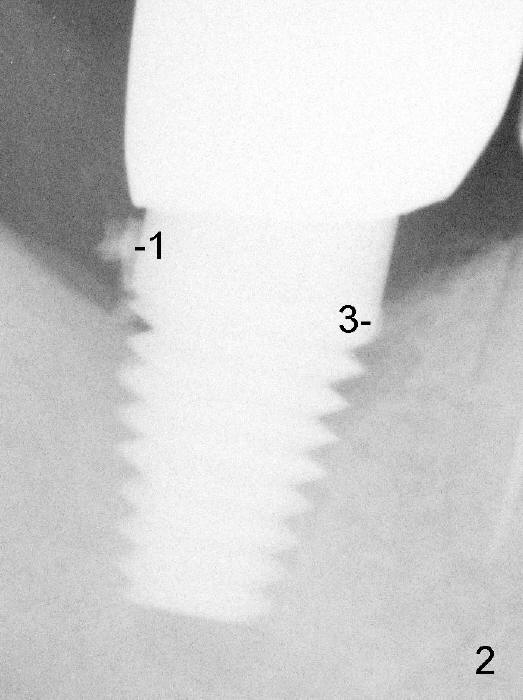

Four months post implantation, a Zirconia crown is cemented with Temp Bond. Two months later, the patient returns for recall. Bitewing shows 3 pieces of residual cement (Fig.1: #1,2,3) . Due to the thick distal gingiva (Fig.1 <), initial effort results in partial removal of the distal cement (Fig.2 (PA): #1). The shallow cement in the mesial aspect is apparently removed, whereas the deep one remains untouched (Fig.2: #3). Further removal is done before discharge without X-ray confirmation.